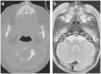

Durante el segundo ingreso se le realizó una TC de las fosas nasales en la que se observó la disminución de la distancia entre ambos procesos nasales del maxilar (fig. 1), incisivo central único congénito (fig. 2a y b) y paladar triangular (fig. 3) con cresta central (fig. 4), hallazgos compatibles con ECOP.

El diagnóstico definitivo de la ECOP se realiza mediante TC de las fosas nasales. Los hallazgos radiológicos consisten en un crecimiento excesivo del proceso nasal del hueso maxilar, un paladar duro hipoplásico con morfología triangular (fig. 3) y un consecuente estrechamiento del orificio piriforme (fig. 1).

Se considera diagnóstico si el diámetro transverso máximo del orificio piriforme es menor de 11mm1,4,6. Belden et al concluyeron que la ECOP es el resultado de un estrechamiento de toda la cavidad nasal en su porción inferior, más marcada en su abertura anterior1.